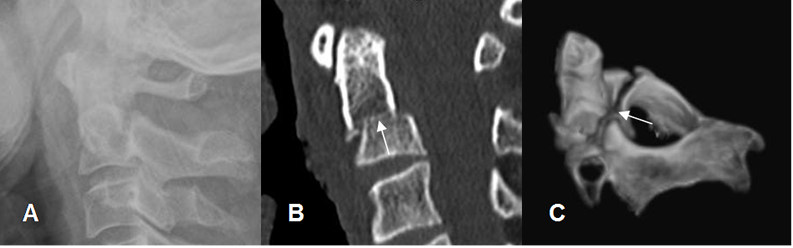

Fig 165. Alteración de apófisis espinosas.

A: Rx AP y B: TAC reconstrucción sagital. No visualización de la apófisis espinosa de C6, por anterolistesis traumática G II.

La TAC es la modalidad de elección en la valoración inicial, de la columna cervical en pacientes politraumatizados y ha demostrado ser costo-efectiva. (38, 41, 42). Es mas sensible que la Rx simple para detectar fracturas y permite realizar reconstrucciones 3D y caracterizar las lesiones. (40, 41). (Fig 173 y 174).

Fig 173. Fractura no vista en Rx.

A: Rx lateral. Rectificación cervical, sin desalineación, ni fracturas. Calcificación en la parte anterior del disco C5-C6.

B: TAC axial. Fractura oblicua y no desplazada en la lámina izquierda de C5, no sospechada con la Rx.